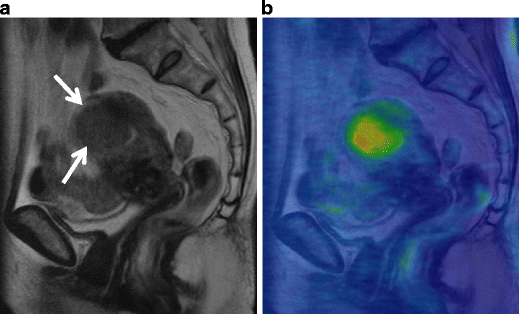

Endometrioid carcinoma in a 30-year-old woman. a Sagittal T2-weighted image demonstrates an ill-defined area of decreased intensity in the thickened endometrium (arrows). b Postcontrast T1-weighted image demonstrates poorly enhanced tumor in the endometrium (arrows). In both images, the endometrial-myometrial border is well preserved, suggesting the tumor is confined within the endometrium

Endometrioid carcinoma in 53-year-old woman. a Sagittal T2-weighted image demonstrates an ill-defined endometrial tumor. The endometrial-myometrial border is almost entirely obscured, suggesting the myometrial invasion by the tumor. b Early-phase image of dynamic enhanced T1-weighted clearly demonstrates inner myometrium of strong enhancement (arrowheads), which become irregular by invading tumor